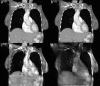

Methods: With the dual-view DTS technique, limited angle scans are performed and projection images are acquired in two orthogonal views: PA and lateral. The dual-view projection data are used together to reconstruct 3D images using the maximum likelihood expectation maximization iterative algorithm. In this study, projection images were simulated or experimentally acquired over 360° using the scanning geometry for cone beam computed tomography (CBCT). While all projections were used to reconstruct CBCT images, selected projections were extracted and used to reconstruct single- and dual-view DTS images for comparison with the CBCT images. For realistic demonstration and comparison, a digital chest phantom derived from clinical CT images was used for the simulation study. An anthropomorphic chest phantom was imaged for the experimental study. The resultant dual-view DTS images were visually compared with the single-view DTS images and CBCT images for the presence of image artifacts and accuracy of CT numbers and anatomy and quantitatively compared with root-mean-square-deviation (RMSD) values computed using the digital chest phantom or the CBCT images as the reference in the simulation and experimental study, respectively. High-contrast wires with vertical, oblique, and horizontal orientations in a PA view plane were also imaged to investigate the spatial resolutions and how the wire signals spread in the PA view and lateral view slice images.

Results: Both the digital phantom images (simulated) and the anthropomorphic phantom images (experimentally generated) demonstrated that the dual-view DTS technique resulted in improved spatial resolution in the depth (PA) direction, more accurate representation of the anatomy, and significantly reduced artifacts. The RMSD values corroborate well with visual observations with substantially lower RMSD values measured for the dual-view DTS images as compared to those measured for the single-view DTS images. The imaging experiment with the high-contrast wires shows that while the vertical and oblique wires could be resolved in the lateral view in both single- and dual-view DTS images, the horizontal wire could only be resolved in the dual-view DTS images. This indicates that with single-view DTS, the wire signals spread liberally to off-fulcrum planes and generated wire shadow there.